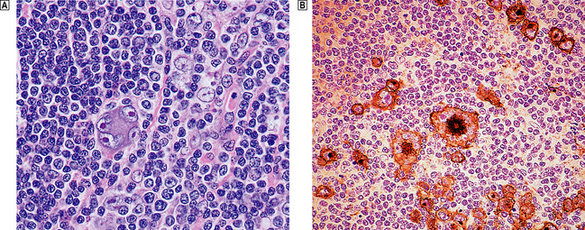

Complications

Lymphadenopathy in HIV infection may not be due solely to immune dysregulation and aberrant lymphocyte proliferation; a variety of neoplastic and infective conditions may also affect the lymph node. Lymphadenopathic Kaposi’s sarcoma and high-grade B-cell non-Hodgkin’s lymphoma (often with Burkitt-like morphology) are common. A wide variety of infectious agents may cause lymph node enlargement, of which atypical mycobacterial infection is frequently encountered (Fig. 22.5). Pneumocystis jiroveci may also be encountered in the lymph nodes of severely immunosuppressed patients.

image

Fig. 22.5 Mycobacterial infection of a lymph node in AIDS. image Aggregates of large histiocytes with foamy cytoplasm. image A similar area stained for acid-fast bacilli (Ziehl–Neelsen stain), demonstrating numerous mycobacteria (stained red; arrowed).